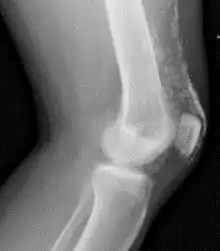

Magnetic resonance imaging may be useful to guide muscle biopsy and to investigate involvement of internal organs;[11] X-ray may be used to investigate joint involvement and calcifications.[12]